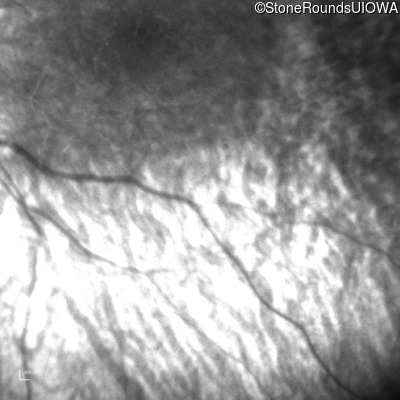

Infrared Fundus Photograph - Right -

No Light Perception

Infrared Fundus Photograph - Left -

Light Perception